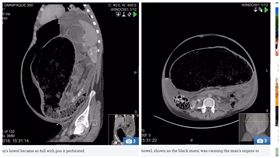

被糞便塞爆!男直腸脹到18公分險死

英國一名24歲男子罹患慢性便秘長達4年,也會定時到醫...